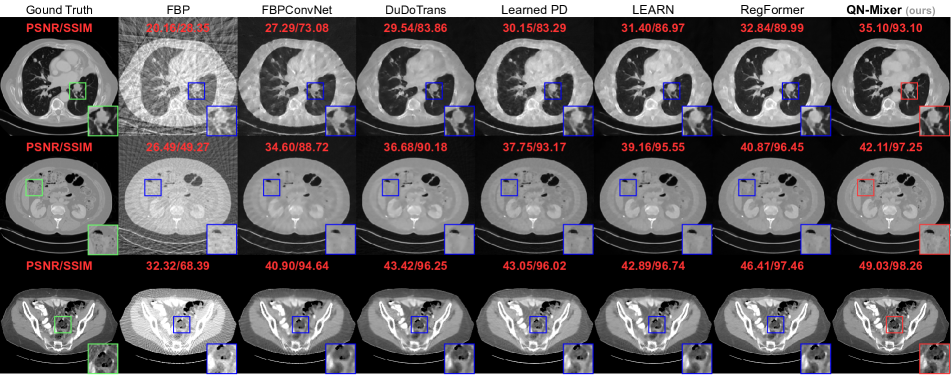

Figure 5: Visual comparison on DeepLesion of state-of-the-art methods. Rows display results under different conditions: (nv=64,N1)subscript𝑛𝑣64subscript𝑁1(n_{v}=64,N_{1}) and (nv=128,N1)subscript𝑛𝑣128subscript𝑁1(n_{v}=128,N_{1}). Display windows are set to [1000,800]1000800\left[-1000,800\right] HU for the first row and [200,300]200300\left[-200,300\right] HU for the second row.

Quantitative comparison.  We compared our model with state-of-the-art baselines on two public datasets. For AAPM, models were trained and tested across three projection views (nv{32,64,128}subscript𝑛𝑣3264128n_{v}\in\{32,64,128\}) and three noise levels, namely no noise N0=0subscript𝑁00N_{0}=0, low noise N1=106subscript𝑁1superscript106N_{1}=10^{6}, and high noise N2=5×105subscript𝑁25superscript105N_{2}=5\times 10^{5} (see Tab. 1). For DeepLesion, models were trained and tested on the same three projection views and a noise level of N1=106subscript𝑁1superscript106N_{1}=10^{6} (see Tab. 2). Visual results are provided in Fig. 4 (AAPM) and Fig. 5 (DeepLesion). Impressively, our method achieves state-of-the-art results on DeepLesion across all projection views. It outperforms the second-best baseline, RegFormer, with an average improvements of +2.232.23+2.23 dB in PSNR and +1.021.02+1.02% in SSIM. On AAPM without noise, we achieve state-of-the-art results across all projection views and improve the second best by an average +1.651.65+1.65 dB and +0.58%percent0.58+0.58\%. In the presence of low noise, QN-Mixer achieves state-of-the-art results performance in all cases except nv=128subscript𝑛𝑣128n_{v}=128 with 0.110.11-0.11 dB and shows an average improvements of +0.330.33+0.33 dB and +0.350.35+0.35% over RegFormer. With high noise, our method performs nearly on par in nv=32subscript𝑛𝑣32n_{v}=32 (0.020.02-0.02 dB and 0.290.29-0.29%), achieves state-of-the-art in nv=64subscript𝑛𝑣64n_{v}=64 (+0.20.2+0.2 dB and +0.080.08+0.08%), and competes closely in nv=128subscript𝑛𝑣128n_{v}=128 (0.010.01-0.01 dB and +0.080.08+0.08%). As noise increases, we attribute the decline in improvement to the compressed gradient information in the latent BFGS, influenced by sinogram changes, and the utilization of the FBP algorithm instead of the pseudo-inverse.

Visual comparison.  As it can be seen on Fig. 4 and Fig. 5, FBPConvNet and DuDoTrans exhibit noticeable blurry images with severe artifacts when nv=32subscript𝑛𝑣32n_{v}=32. While Learned PD and LEARN show satisfactory performance, they struggle with intricate details, like in the liver and spine. In contrast, RegFormer produces high-quality images but faces challenges in generalizing to OOD data. QN-Mixer excels in producing high-quality images with fine details, even under challenging conditions such as nv=32subscript𝑛𝑣32n_{v}=32 views and OOD data.

Fig. 10 displays supplementary visualizations of our approach on AAPM. Our method consistently produces high-quality reconstructions across all views. Notably, among state-of-the-art techniques, QN-Mixer excels in reconstructing fine-grained details. For instance, it accurately captures small vessels in the first row, delicate soft tissue structures in the second row, and sharp boundaries in the third row.

In Fig. 11, we showcase additional visualizations of our method applied to DeepLesion. QN-Mixer demonstrates superior performance across all views, yielding high-quality reconstructions. This is particularly evident in the challenging scenario of 323232 views, where our method outperforms others in capturing fine-grained details, such as small vessels and lesions. Importantly, these results are achieved with fewer iterations compared to alternative unrolling networks like RegFormer.